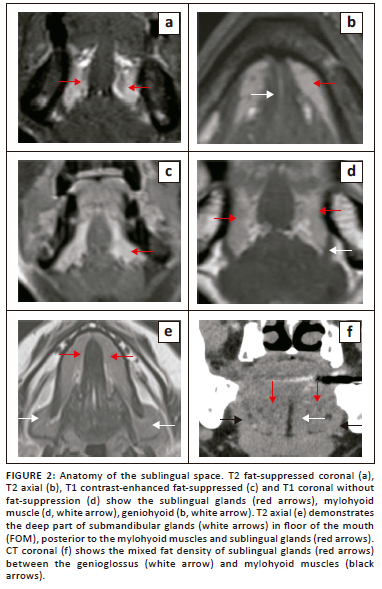

The FOM is an important region of the oral cavity, located inferior to the oral tongue, bound anteriorly and laterally by the inner mandibular gingiva and inferiorly by the mylohyoid and geniohyoid muscles (Figure 1 and Figure 2). The posterior margin of the FOM corresponds to the attachment of the anterior tonsillar pillar to the tongue.

The sublingual space (SLS) is the major dominant deep neck anatomical space and is also referred to as the FOM, divided into bilateral spaces by the frenulum of the tongue.1,2,3,4 The SLS lies lateral to the genioglossus and geniohyoid muscles and superior to the mylohyoid muscle (Figure 1d and Figure 2). The contents of the SLS are fat, the sublingual glands, the lingual nerve (branch of V3 trigeminal nerve), lingual vessels, branches of the glossopharyngeal and hypoglossal nerves (IX and XII cranial nerves), the superior most part of the submandibular gland, Wharton's duct (submandibular) and part of the hyoglossus muscle.3,5,6 The SLSs communicate freely with each other anteriorly and communicate with the submandibular spaces inferiorly through the gap between the free posterior margin of the mylohyoid and hyoglossus muscles4,6,7 (Figure 1b and Figure 2e). Extension of disease can occur from the submandibular to the parpharyngeal space through the communicating channels.7,8

The sublingual glands are formed by smaller glands and are drained by short ducts in the FOM/SLSs. These glands are best visualised on T2-weighted short-tau inversion recovery (T2-STIR) and post-contrast MRI8 (Figure 2a, c). The submandibular (Wharton) ducts pierce the mylohyoid muscles and open in the FOM, on either side of the frenulum. The duct opening can be occluded by calculi or tumours and patients can present with features of the obstructive submandibular adenitis.

The mylohyoid muscle is an important anatomical landmark in the FOM; it separates the SLS above from the submandibular space below, and it lies superior to the anterior belly of the digastric muscle (Figure 1 and Figure 2d). This is a paired sling-like structure, originating from the mylohyoid ridge at the medial aspect of the body of the mandible and forming the muscular floor of the oral cavity. The bulk of the muscle fibres (anterior and middle) attach to the midline raphe, which extends from the mandibular symphysis to the hyoid bone and the posterior one-fourth of the fibres attach to the anterior surface of the hyoid bone.1,6,7